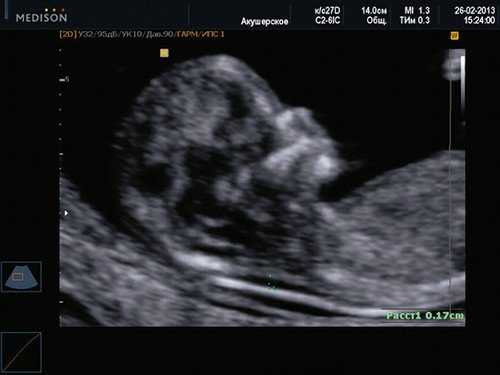

Цель 3D-ультразвукового исследования состоит в создании объемного изображения в отличие от двухмерного метода, создающего плоскостные сечения [6, 11]. Объемная картина получается при сканировании смежных сечений — это объем пространства пирамидальной формы (рис. 3, 4).

Рис. 3. Плод, 31 неделя, 3D-ультразвуковое исследование / Fig. 3. Fetus, 31 weeks, 3D

Рис. 4. Плод, 32 недели, 3D-ультразвуковое исследование / Fig. 4. Fetus, 32 weeks, 3D

Время сканирования в среднем составляет от 3 до 10 с в зависимости от важности объемной информации и требуемого качества изображения.